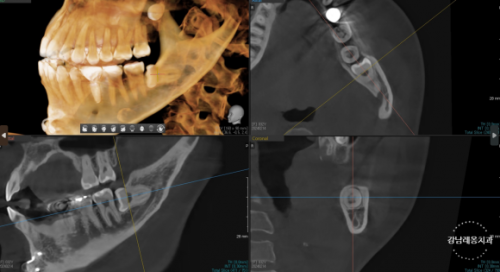

(*필요하다면 CT촬영 추가적으로

진행할 수 있습니다.)

Q. 파노라마를 찍었는데 CT는 왜 또 찍나요❓

파노라마 엑스레이와 CT의 기능이 다릅니다.

파노라마 엑스레이로 매복치나

사랑니의 존재 여부는 확인이 가능하나

2차원적인 사진이기 때문에 진짜 주변 구조물과 닿아있는지

아니면 사진상으로만 겹쳐보이는 것인지 확인하기 어렵습니다.

따라서 필요에 따라

3차원적으로 치아를 확인할 수 있는

CT촬영을 진행하게 됩니다.

파노라마 엑스레이 촬영 (2차원)

CT촬영 (3차원)